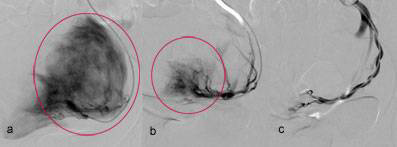

Resultat

Die Verstopfung der Gefässe erfolgt unter ständiger Bildkontrolle mittels einer modernen Durchleuchtungsanlage. Hierüber wird zum einen gewährleistet, dass wirklich nur das Tumorgefäss behandelt und verschlossen wird, zum anderen wird sichergestellt, dass der Eingriff erst dann beendet wird, wenn wirklich alle Tumorgefässe behandelt und verstopft wurden.

• Im zeitlichen Ablauf sieht man eine kräftige Kontrastmittelaufnahme des Tumorknoten vor der Behandlung (a)

• Diese wird im Verlauf weniger (b)

• Am Ende der Behandlung  ist sie gar nicht mehr nachweisbar. Alle Tumorgefässe wurden somit erfolgreich blockiert (c)